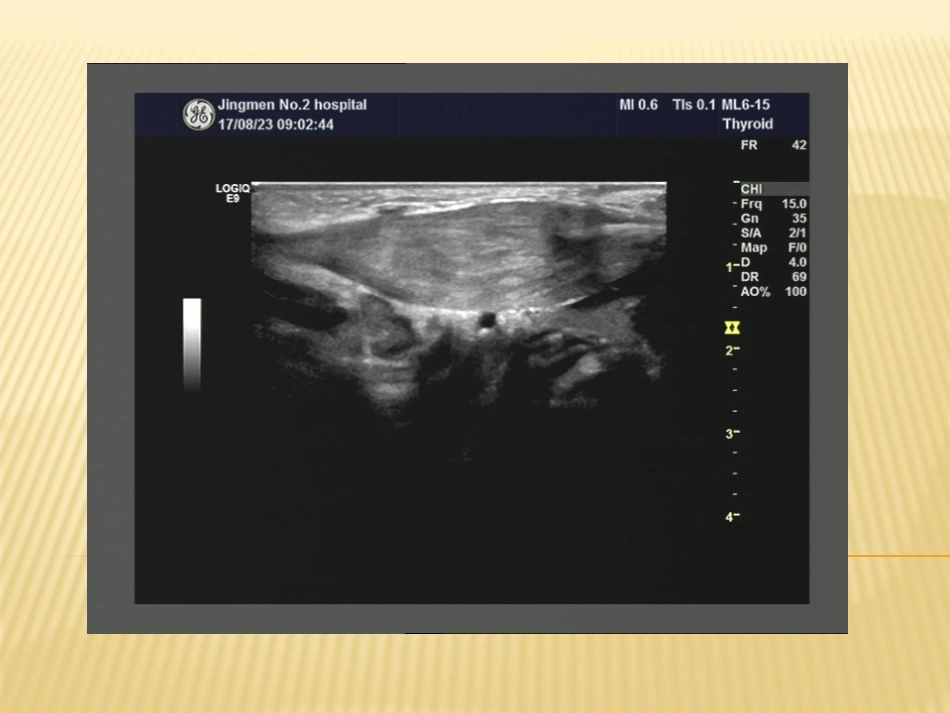

1个月的宝宝,左侧颈部可触及一包块小儿斜颈,医学称先天性肌性斜颈(俗称“歪脖子”),是由于一侧胸锁乳突肌纤维性挛缩,导致缩短,颈部向一侧偏斜畸形,同时伴有脸部发育受影响,小于对侧,严重者导致颈椎侧凸畸形。病因不详,可能和下列因素有关(1)分娩时被损伤,一侧胸锁乳突肌因产伤致出血,形成血肿后机化,继而挛缩。(2)宫内胎位不正,使一侧胸锁乳突肌承受过度的压力,致局部缺血,继而过度退化,为纤维结缔组织所替代。(3)因产伤引起无菌性炎症,致肌肉退行性变和瘢痕化,而形成斜颈。(4)出生时胸锁乳突肌内静脉的急性梗阻有关。发病机制尚不清楚主要有宫内压迫学说:系胎儿在宫内胎位不正引起的压力改变所致。血运受阻学说:供应胸锁乳突肌的动静脉支闭塞引起肌肉的纤维化。遗传学说:约1/5的患儿有家族史,且伴有其他部分的畸形。产伤学说:斜颈多发于难产分娩的病例特别是臀位产约占3/4。患儿出生1周后,病侧颈前部沿胸锁乳突肌可触到一质硬无痛的肿块,2~3周后出现头向患侧倾斜,下颌转向健侧,颈部活动受限,随年龄增大,肿块可逐渐变小,经2~6个月消失后,肌肉变成硬韧索条状。局部皮肤正常,无全身症状。B超检查对比两侧胸锁乳突肌厚薄,质地,有助于鉴别是否肌性斜颈。患者胸锁乳突肌成梭形肿大,厚度增加,病变部位内部结构模糊,肌束纹理紊乱或消失,呈不均匀高、低混合性回声,但肌外膜尚保持连续。CDFI:早期较丰富,后血流信号逐渐减少至消失。非肿块型肿块型1.骨性斜颈:颈椎异常如寰枢椎半脱位,半椎体等X线继续检查可确诊,胸锁乳突肌不挛缩。2.颈部炎症:遇见淋巴结肿大,有压痛及全身安排症状,胸锁乳突肌无挛缩。3.软组织肿瘤。本病治疗越早效果越好。婴儿期采用保守治疗,大多数疗效满意。1岁后,若非手术治疗无效则采用手术治疗。一般认为3岁以上,面部畸形难以完全恢复正常。